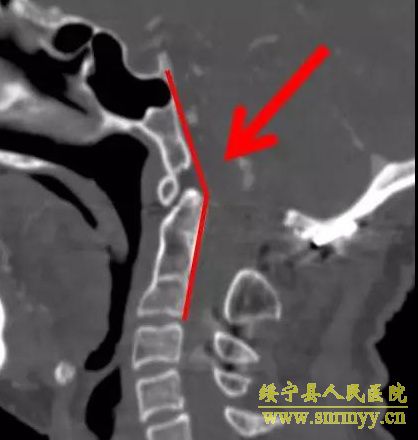

9月2日,我院神经外科在解放军昆明总医院封亚平教授的指导下,成功实施县内首台上颈椎、颅颈交接区手术,这标志着我院神经外科诊疗技术又迈上了一个新台阶。 40岁女性患者,因“头疼头晕伴左侧肢体麻木3年余,加重1月”入院,诊断为环枕畸形合并小脑扁桃体下疝。MRI及CT显示:枕颈融合,寰枢关节脱位,颅底陷入,颅颈角明显变小,小脑扁桃体下疝、延颈交界脊髓明显受压(如图下图所示),此病的症结是那块骨头(红色箭头处)压迫了神经! 想要解决问题,自然就得把那块骨头“掰”下来。骨头虽小,真要把它“掰”下来却绝非易事,需要把颈1-2的小关节撑开,但是,患者的小关节后面还有很粗大的动脉血管(蓝色箭头)挡着,手术难度相当大! 经解放军昆明总医院封亚平教授会诊,我院神经外科为该患者实施了后入路枕骨大孔区减压、寰枢椎脱位复位、枕颈固定、植骨融合术,手术用时短短1.5小时,出血量仅50ml。病人术后神经压迫症状明显改善,第一天开始进食,第二天即可下床活动。 (斜坡颈椎角增大到正常) (术后复查CT及MRI显示寰枢关节脱位复位理想,颅颈角增大基本正常,脊髓受压解除。) (术中无血管、神经损伤) 寰枕畸形是枕骨大孔区、寰枢椎骨质发育异常伴神经系统、椎动脉及附近软组织发育异常的一种先天性畸形疾病。寰枕畸形主要包:扁平颅底、颅底凹陷、寰枕融合、颈椎分节不全、寰枢椎脱位、小脑扁桃体下疝畸形。寰枕畸形可继发于畸形性骨炎、软骨病、佝偻病等。寰枕畸形患者早期临床表现为颈短、头颈痛、活动受限等。对于颈部粗而短的人群而言,寰枕畸形的发病可能相较一般人更高。原因在于,颈部粗短的人在转头活动的过程中,关节的活动度比较大,磨损的程度也更高,因而更容易发病。寰枕畸形合并小脑扁桃体下疝及脊髓空洞症为先天性发育不良所致,成年起病,无任何药物可治疗,手术是唯一有效的治疗办法。起初,患者会逐渐出现颈肩部疼痛,手臂麻木、无力,行走不稳等症。若不及时治疗,晚期预后会很差。(图为 邓泽亮 编辑 雅玲) 神经外科电话0739-2570859 科主任邓泽亮13975968148 副主任黄敏15211991811 |